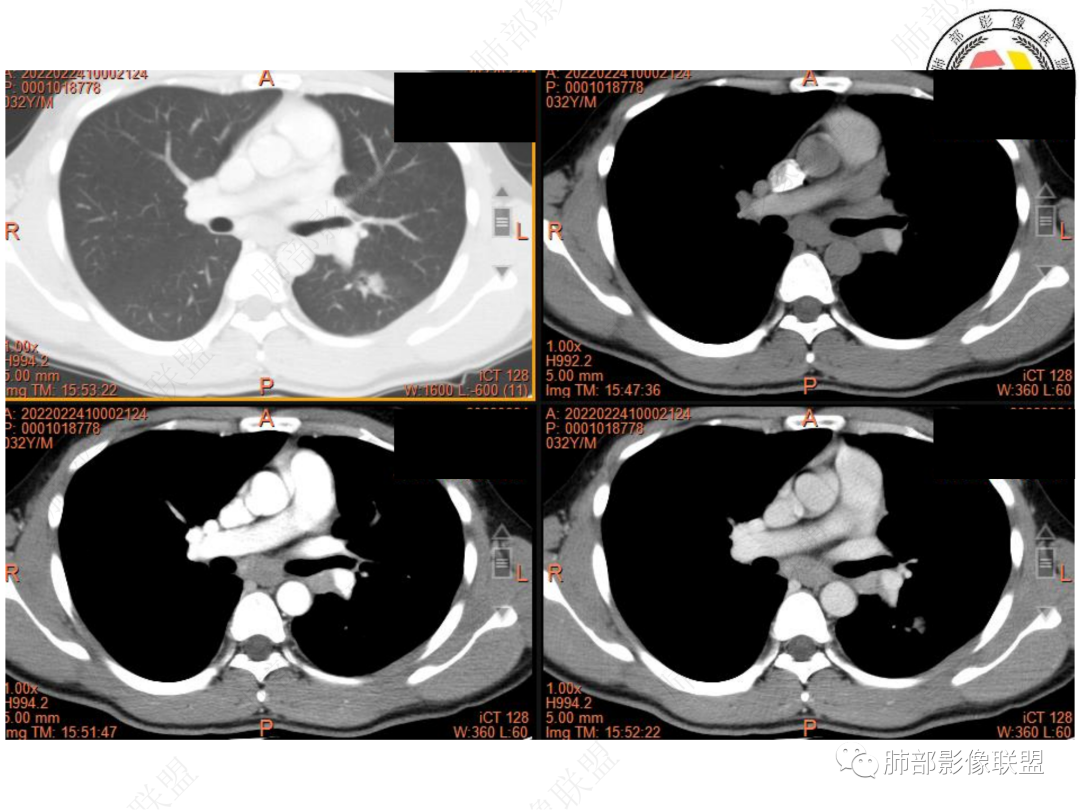

3. CT示左肺下叶背段孤立实性密度结节影,边缘比较清楚光滑,总体呈现膨隆感,未见分叶毛刺,少张力,部分层面病灶边缘呈现较清楚磨玻璃样密度影,并于磨玻璃影病灶内可见多发小空泡,未见钙化或空洞,增强后病灶显示不均匀强化,未见低密度液化区。未见卫星病灶。

左肺门及纵隔内多发淋巴结肿大,大部分淋巴结显示融合,强化不均匀,内见低密度区,疑液化坏死。纵隔内淋巴结部分周围脂肪间隙不清晰。大血管及左肺主支气管未见受侵改变。

5. 此病例青年男性,纵隔淋巴结环形强化,易先入为主诊断结核。但左肺下叶背段病灶密度均匀,强化明显,整体具备膨隆感,缺少炎性病灶的平直征,病灶周围未见卫星灶,应想到新生物可能。纵隔及左肺门肿大淋巴结,虽有部分淋巴结环形强化特点,但是部分淋巴结周围血管脂肪间隙小时、密度增高,强化明显。至此,亦可与结核的环形强化区分开来。尽管患者年轻,但恶性征象出现时,仍应当高度警惕。